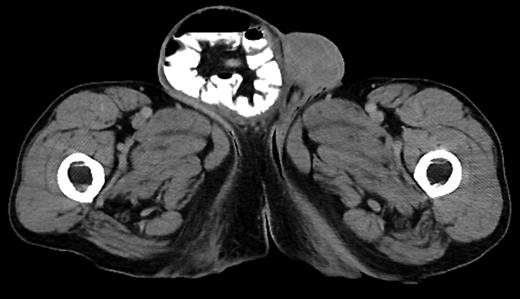

In general, the risk of surgical site infection with bowel surgery is greater than without. Therefore, there may be increased risk of infection at the hernia repair site in this procedure [5]. However, with sparse data available on the subject, there has yet to be any evidence that shows this is the case. As more of these combined procedures are performed, there will eventually be enough data for evidence-based practice (Figure 3).